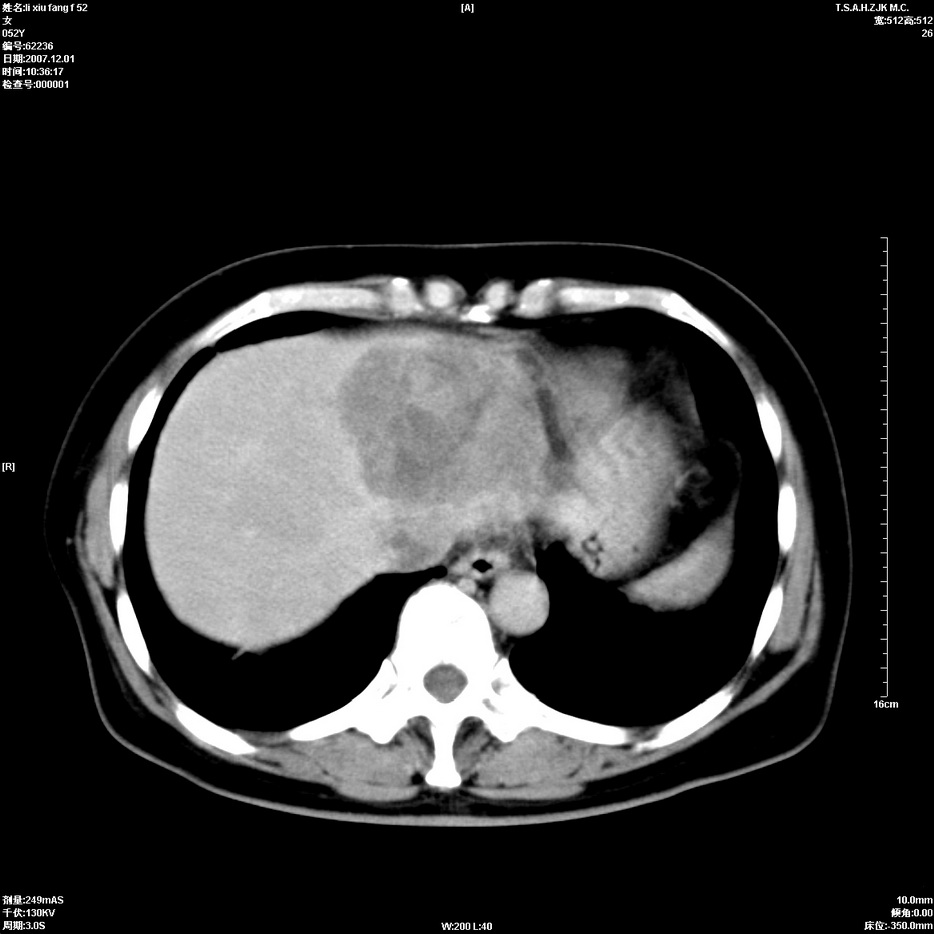

标题: CT12858:女,52岁,胎甲球蛋白861肝左叶占位,肝癌。下腔静 [打印本页]

标题: CT12858:女,52岁,胎甲球蛋白861肝左叶占位,肝癌。下腔静

肝左叶巨大低密度灶肿块,增强符合快进快出表现,有动静脉交通支;静脉期,下腔静脉内有充盈缺损,afp明显升高,支持肝癌并下腔静脉癌栓形成。

支持楼主   门静脉主干及左支癌栓形成

以下是引用拾荒者在2008-4-15 22:57:00的发言:[br]肝左叶巨大低密度灶肿块,增强符合快进快出表现,有动静脉交通支;静脉期,下腔静脉内有充盈缺损,afp明显升高,支持肝癌并下腔静脉癌栓形成。